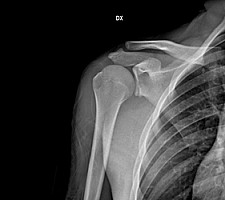

L’instabilità anteriore della spalla rappresenta una patologia molto frequente nella medicina sportiva, soprattutto nei giovani maschi e negli atleti.

Recenti studi biomeccanici hanno dimostrato come già dopo una singola lussazione, si verifichi un’alterazione della cinematica articolare con una modifica della biomeccanica a cui consegue l’aumento del rischio di instabilità recidivante.

Per questo motivo la gestione del primo episodio di instabilità anteriore post traumatica della spalla rappresenta un argomento di grande attualità, in particolare per quella parte di popolazione rappresentata da pazienti giovani e da atleti ad alto rischio.